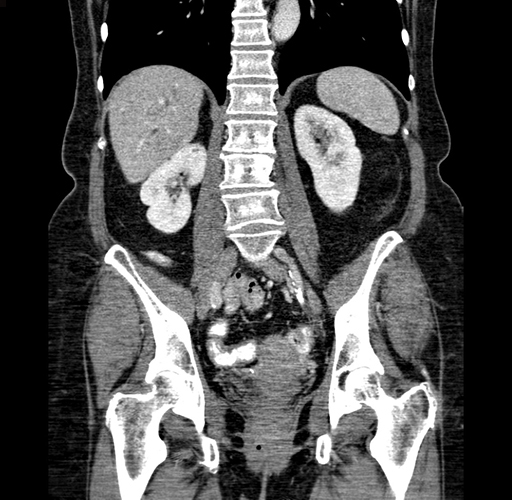

Pre-Chemo: Coronal Venous

Coronal Venous